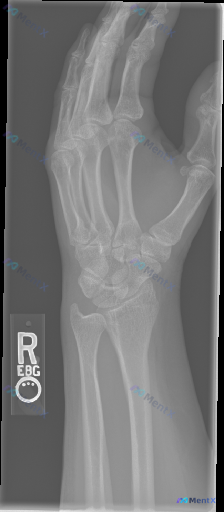

整理到一份右腕关节正位X光片的影像资料及相关分析思路,想和大家讨论一下这种场景下的判断逻辑。 影像所见(整理自报告): - 腕骨序列、形态大致正常,未见明确皮质中断、骨折线或移位 - 桡尺骨远端、掌骨基底部皮质连续,桡腕关节对位良好 - 关节间隙正常,骨密度均匀,未见溶骨或成骨改变 - 周围软组织无...